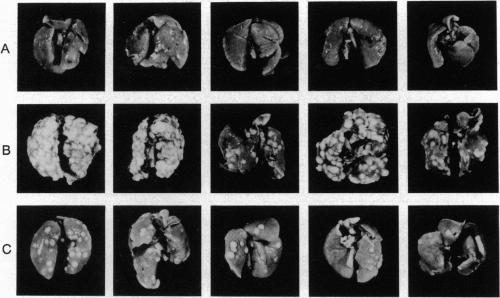

The human papillomavirus type 16 (HPV-16) is a DNA tumor virus highly associated with cervical carcinoma. Viral DNA from HPV-16 is found in primary tumors and their metastatic lesions. To investigate the role of HPV-16 oncoproteins in the development of cancer metastasis, the E6 and E7 genes from HPV-16 were inserted into retrovirus and introduced into nonmetastatic mouse cell lines. Expression of either of the viral genes from HPV-16 made the cells metastatic in nude mice. In contrast, expression of the E6 and E7 genes of HPV type 6 (HPV-6b), which is frequently found in nonmalignant HPV-associated diseases, did not. The metastatic ability of cells transduced with viral genes of HPV-16 did not correlate with their growth rate or sensitivity to destruction by natural killer cells. Our results demonstrate that expression of oncogenic proteins of HPV-16 can cause tumor metastasis and implicate HPV-16 in an important role regarding the progression of HPV-associated human cancers.

人乳头瘤病毒16型(HPV - 16)是一种与宫颈癌高度相关的DNA肿瘤病毒。在原发性肿瘤及其转移病灶中可发现来自HPV - 16的病毒DNA。为了研究HPV - 16癌蛋白在癌症转移发生过程中的作用,将来自HPV - 16的E6和E7基因插入逆转录病毒,并导入非转移性小鼠细胞系。来自HPV - 16的任一病毒基因的表达都使细胞在裸鼠中具有转移性。相比之下,在非恶性HPV相关疾病中常见的人乳头瘤病毒6型(HPV - 6b)的E6和E7基因的表达则不会。用HPV - 16病毒基因转导的细胞的转移能力与其生长速率或对自然杀伤细胞破坏的敏感性无关。我们的结果表明,HPV - 16致癌蛋白的表达可导致肿瘤转移,并表明HPV - 16在HPV相关人类癌症的进展中起重要作用。